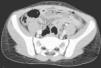

TCMD axial. Hallazgos: engrosamiento mural de un amplio segmento de intestino delgado (ileon) en el hemiabdomen izquierdo, que además asocia un aumento de realce parietal. Pequeña burbuja extraluminal, intraperitoneal, adyacente a la pared abdominal anterior en su vertiente izquierda. Los hallazgos son indicativos de perforación de intestino Delgado.